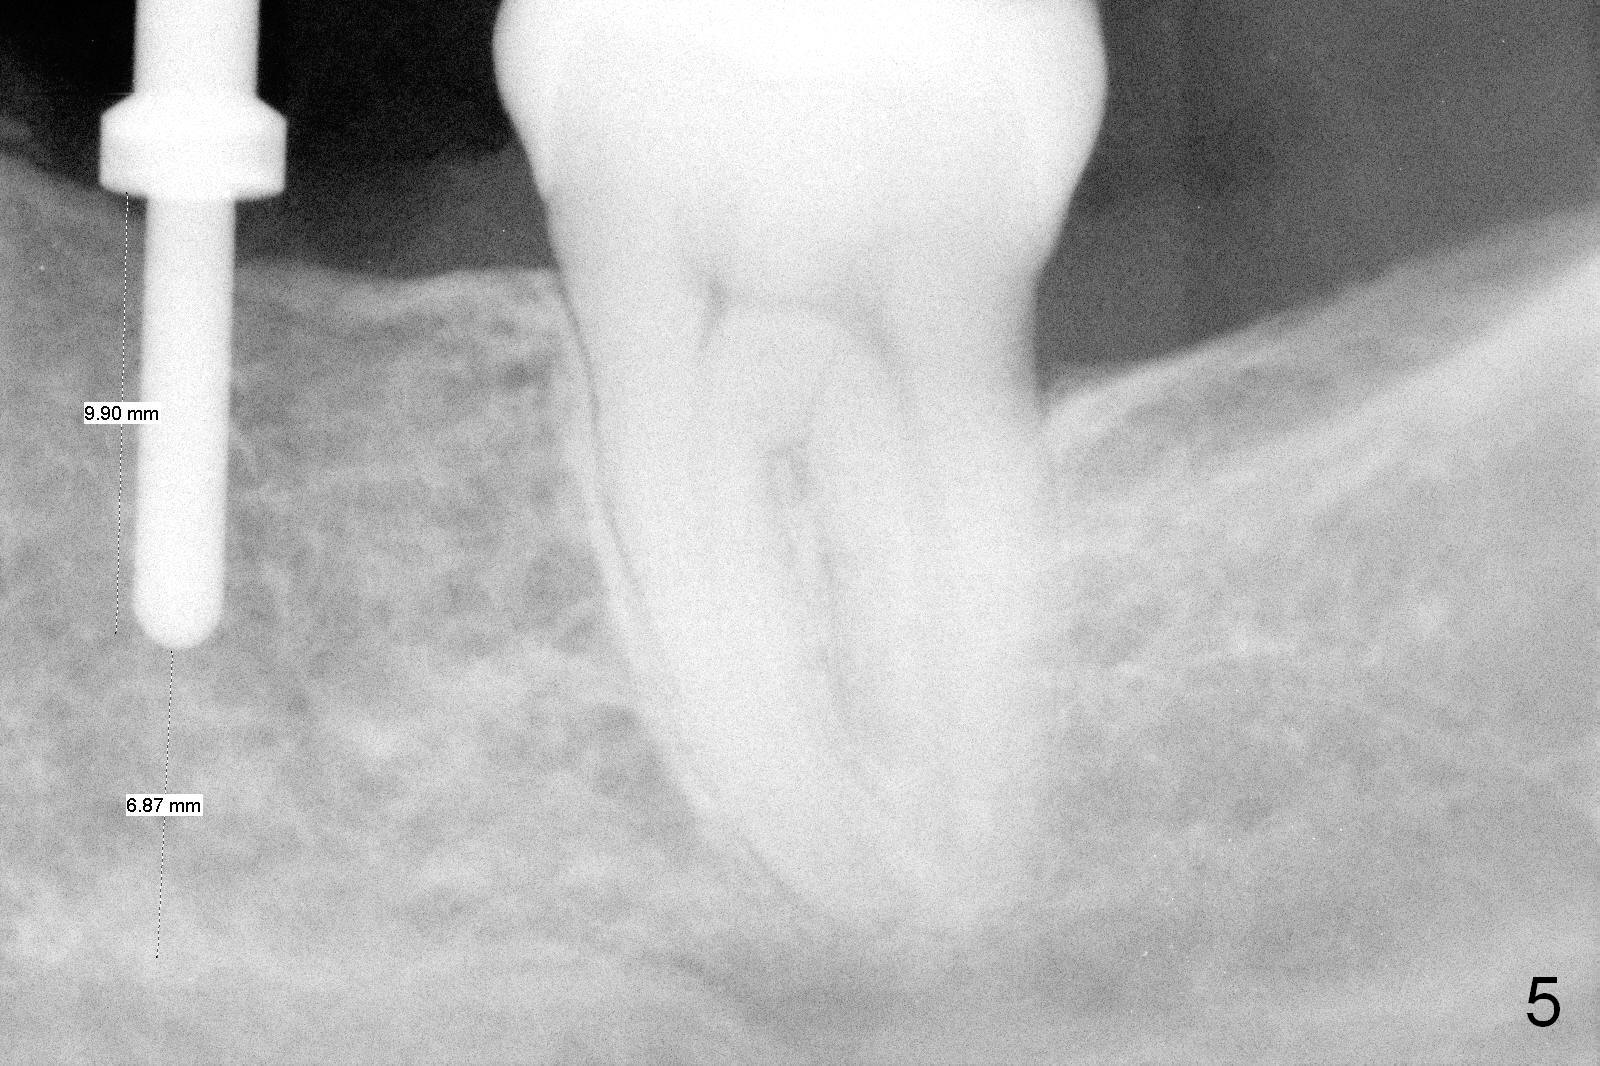

A 44-year-old black lady is a typical dental phobic. She has lost #19 for years with history of traumatic extraction. The ridge is atrophic (Fig.1). She is not comfortable with intraoral X-ray. So CBCT is taken. The coronal section shows that the bone density is low in the coronal ridge (Fig.2 arrowheads). It is difficult to determine the buccolingual width at crest; probably a 5.9x10 mm implant is appropriate (Fig.3). The most useful information from CT is height determination for the implant (Fig.4). The initial osteotomy depth is 10 mm (Fig.5); there is a large safety margin. There is a 2 mm clearance when a 4.5x12 mm implant is placed (Fig.6). Incision is sutured; a 8x4 (3) mm healing abutment is placed (Fig.7 arrowhead), followed by application of perio dressing. The latter remains stable 13 days postop thanks to the holding effect of the healing abutment (Fig.8 H). The wound has apparently healed when the dressing is removed (Fig.9). It appears that the edentulous space is extremely wide. The 4.5 mm implant may not sustain masticatory force. Limited orthodontic treatment appears to be necessary, using the implant as an anchorage to move the neighboring teeth (Fig.10 arrows). In fact the orthodontic treatment is not rendered. A crown is cemented 14 months postop. The cortical bone is thickened around the implant 15 months post cementation (Fig.11).